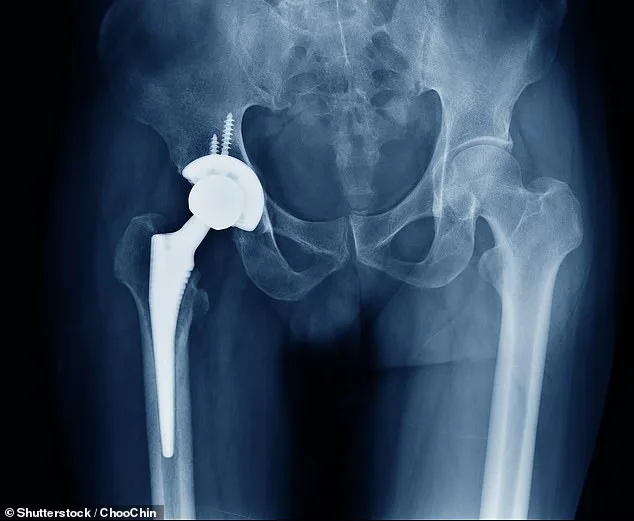

NHS Crisis: Bone Cement Shortage Halts Thousands of Hip and Knee Replacements

A critical shortage of bone cement has triggered the cancellation of thousands of NHS hip and knee replacement operations, threatening to leave patients in prolonged pain and disrupting a healthcare system already strained by waiting lists. The crisis stems from a packaging fault at Heraeus Medical, a key supplier of the cement used to secure artificial joints. This defect has halted production at their main site, with supply delays expected to last at least two months. The impact is profound: 15 of Heraeus's 15 products are affected, including standard fixation cements and antibiotic-loaded variants critical for revision surgeries. With 110,000 hip replacements and 96,000 knee replacements performed in 2023/24, the shortage could delay thousands more, compounding existing waits that already stretch to months.